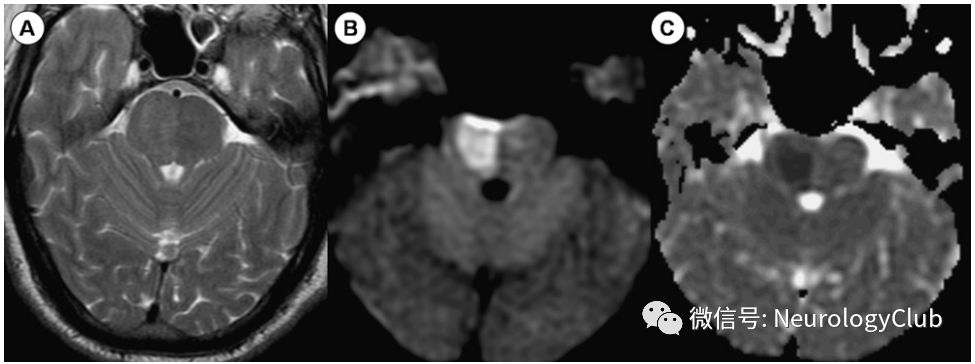

中脑背部梗死(图5)引起复视、垂直性凝视障碍和其他动眼综合征。此外,还可出现耳鸣、听觉过敏和听力丧失。

图5:中脑背侧梗死;62岁患者,表现为眩晕、复视、垂直性凝视麻痹;A:轴向t2加权像未显示任何异常。(B)轴向各向同性扩散加权图像。(C)ADC图显示左侧背部血管区域急性缺血性梗死的典型影像学特征